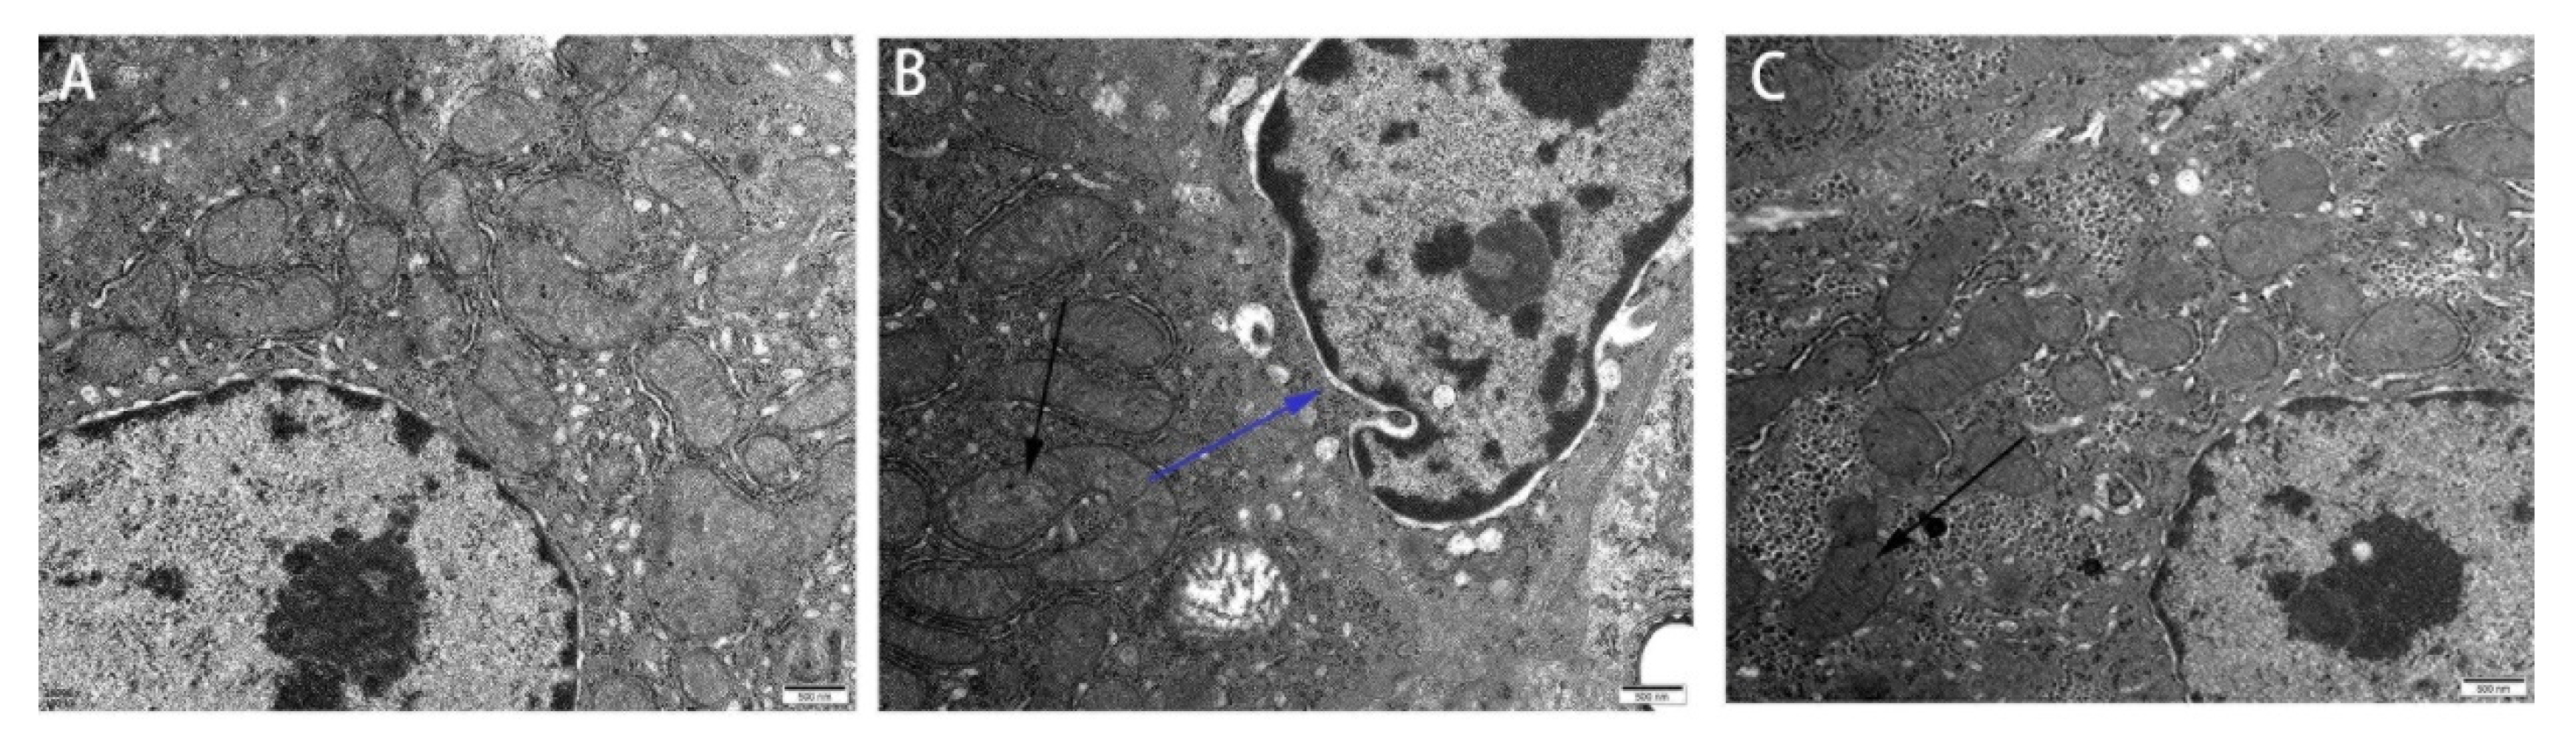

3.1. Effect of Res on the Liver Microstructure and Ultrastructure of Duck Exposed in AFB1